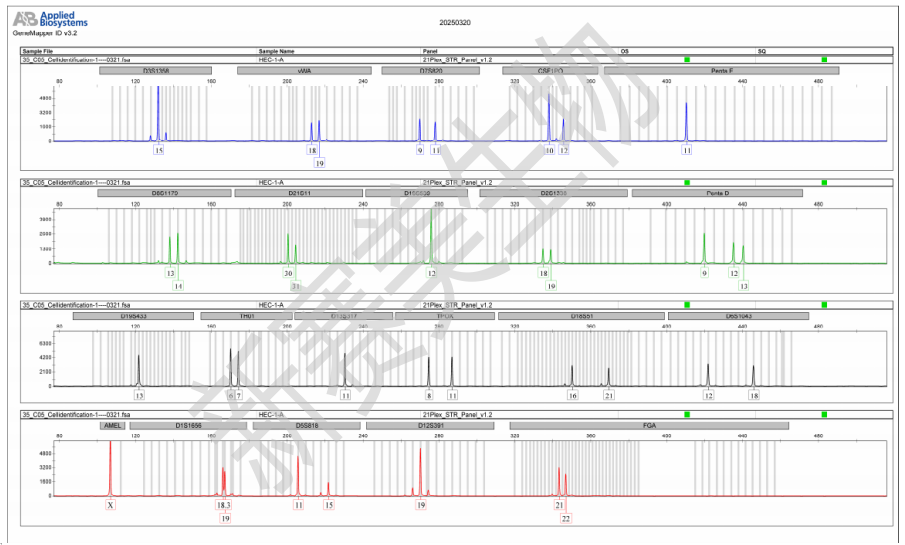

细胞STR检测图谱: